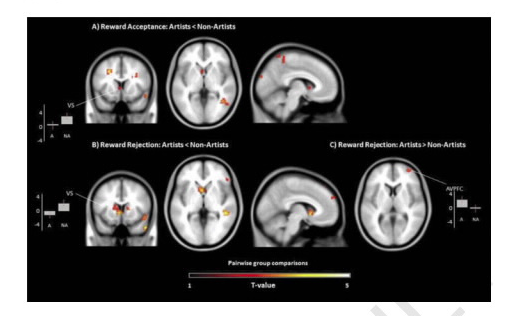

Когда творческие люди находили «денежный» цвет, их мозг показывал очень слабую активность в области полосатого тела — участке, который отвечает за реакцию на вознаграждение. Зато когда художники находили цвета, но не получали за это деньги, повышенная активность наблюдалась в передней префронтальной коре, которая отвечает за выработку дофамина, влияющего на чувство удовлетворения.

Исследователи заключили, что мозг творческих людей проявляет интерес только к самому процессу, не беря в расчет материальное вознаграждение. Кроме того, «художники» могут работать гораздо лучше, когда знают, что не получат за это деньги.